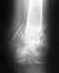

Re: перелом верт.впадины

послал Alexander Chelnokov 10 Июль 2007, 06:53

Если есть болезненные проявления, то нужно. Похоже, нет перспективных вариантов, кроме замещения сустава.